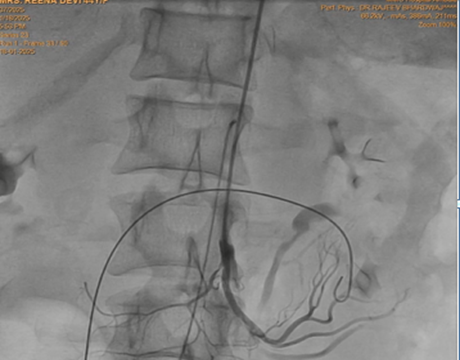

Keeping in view the possibility of Nutcracker syndrome (NKS). patient was taken up for percutaneous treatment. Right femoral vein puncture was done. Femoral vein angiography was done to see inferior vena cava (IVC), (Fig.1) to have idea of origin of left renal vein. Femoral artery access was also taken and left renal arteriography was done to trace renal vein in venous phase, but it could not be visualised. Since renal vein was not visualised, blind entry was done with terumo wire passed through right Judkins (JR)catheter. Catheter was then negotiated into LRV and venography was done (Fig. 2). It showed markedly dilated left gonadal vein (LGV), and left ovarion vein (Fig 3). Hardly any contrast was entering into IVC, due to compression by superior mesenteric artery (SMA). It was decided to put a stent in LRV across the compressed segment. To properly define the site of obstruction and stent placement, a JR catheter was placed in SMA (Fig 4), from left brachial artery approach. Self-expanding venous stent was then deployed, size 14x 60 mm. (Fig 5). LRV angio was then done which showed free flow of contrast into IVC and minimal reflux into LGV (Fig. 6). If, large reflux persisted, then coiling of LGV would have been required.

Figure 4: Catheter in superior mesenteric vein, from left brachial artery approach, as marker to guide the position of stent.